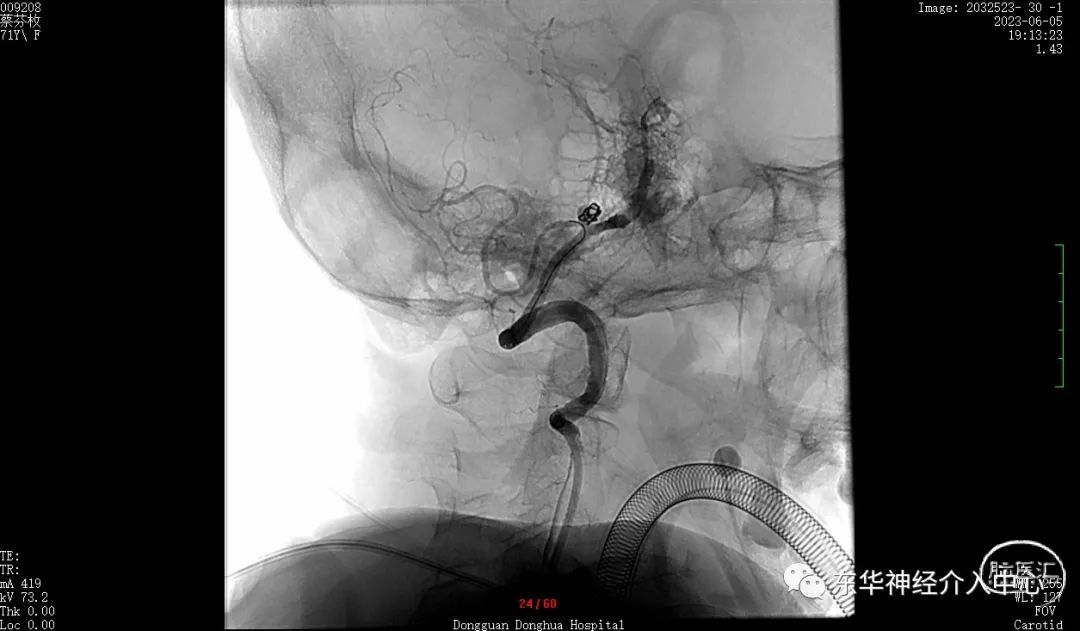

如此信心大增。继续填塞。终于满意的将动脉瘤栓塞,动脉瘤完全不显影。

换一个角度看弹簧圈的形态与动脉瘤的形态基本一致了。

可见载瘤动脉内微导丝与动脉瘤有间隙,说明动脉瘤成蓝非常满意。